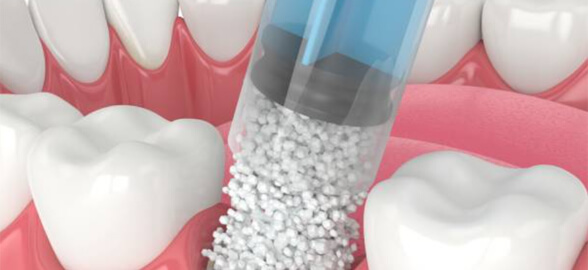

La regeneración ósea en odontología es fundamental para una variedad de tratamientos, desde la colocación de implantes dentales hasta la restauración de defectos óseos causados por